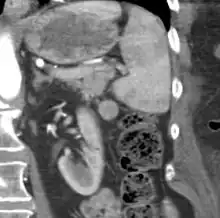

CT scan of an accessory spleen (circular object in center of image) between the spleen and left kidney. | |

An accessory spleen is a small nodule of splenic tissue found apart from the main body of the spleen. Accessory spleens are found in approximately 10 percent of the population[1] and are typically around 1 centimetre in diameter. They may resemble a lymph node or a small spleen. They form either by the result of developmental anomalies or trauma.[2] They are medically significant in that they may result in interpretation errors in diagnostic imaging[2] or continued symptoms after therapeutic splenectomy.[1] Polysplenia is the presence of multiple accessory spleens rather than one normal spleen.

If splenectomy is performed for conditions in which blood cells are sequestered in the spleen, failure to remove accessory spleens may result in the failure of the condition to resolve.[1] During medical imaging, accessory spleens may be confused for enlarged lymph nodes or neoplastic growth in the tail of the pancreas,[5] gastrointestinal tract, adrenal glands or gonads.[2]